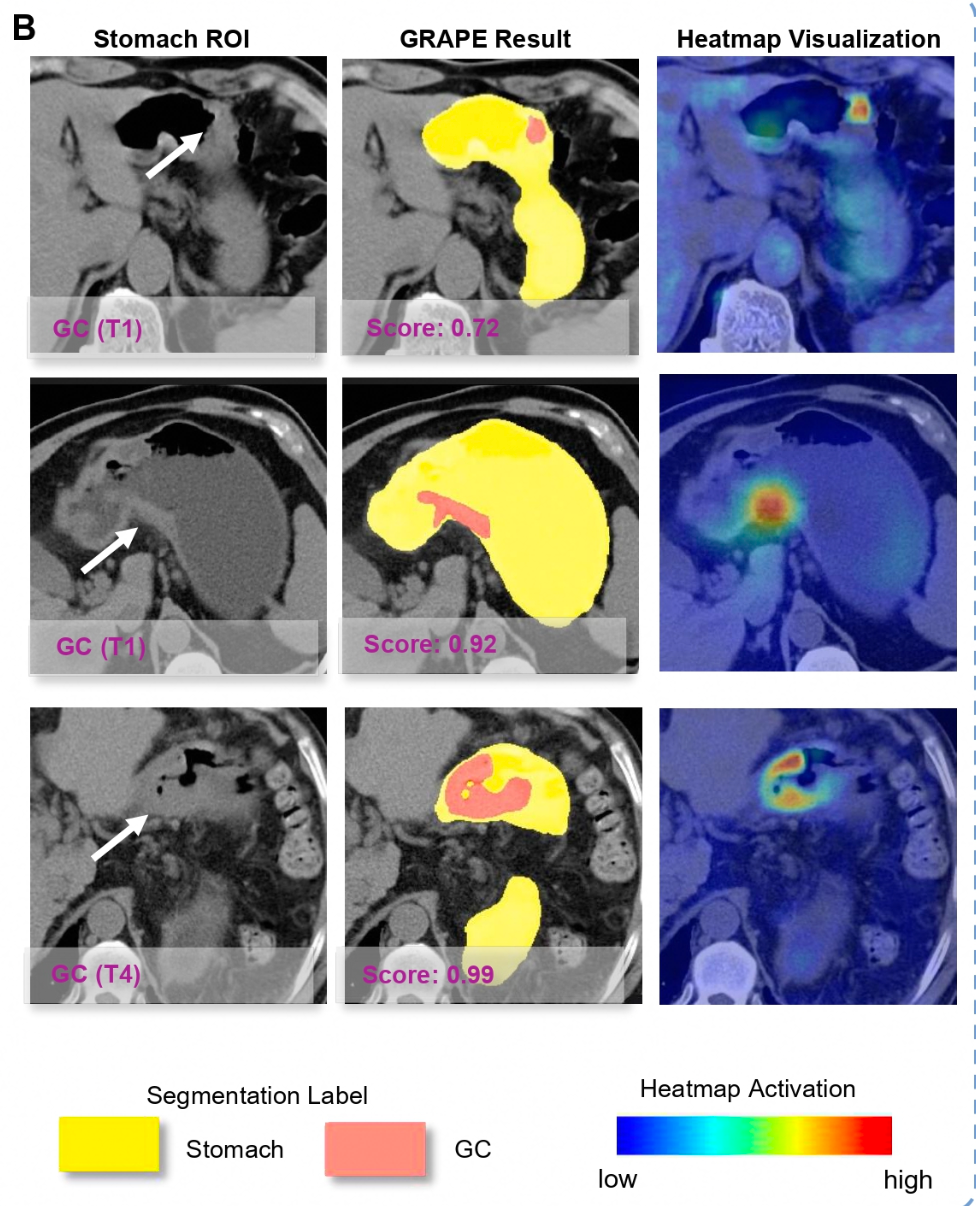

DAMO GRAPE的敏感性和特异性分别达到85.1%和96.8%,相比放射科医生分别提升21.8%和14.0%。这令平扫CT识别早期胃癌首次成为可能,也让“平扫CT+AI”在多癌筛查上更进一步。

在两家地区医院的模拟机会性筛查试验中,DAMO GRAPE模型精准、高效识别胃癌高危人群,胃癌检出率分别达到24.5%与17.7%,且检出病例中约四成为无症状胃癌患者。

AI能识别各阶段胃癌